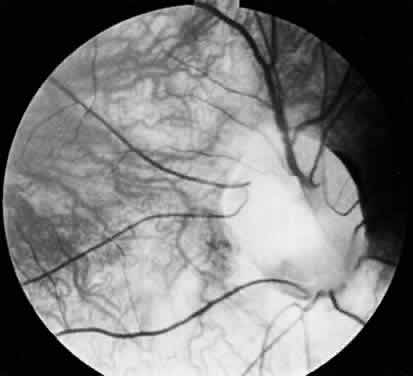

In optic nerve coloboma (Fig. 7) the optic disc is enlarged, frequently oval vertically, and excavated.57 The colobomatous defect may involve the entire disc or just the inferior portion. The excavated region is decentered inferiorly and may extend to involve the choroid and retina. When it does, the eye is often microphthalmic.57 When the entire disc is involved, the inferior region is excavated to a greater extent than the remainder of the disc, confirming its colobomatous nature. The retinal vessels may radiate from the disc in a spokelike fashion, with fewer bifurcations than normal.57 An association between optic nerve colobomas and basal encephaloceles has been reported58,59; however, examination of the literature reveals only a few photographically documented cases, and the reported association may be because of its confusion with morning glory disc anomaly.60,61

Fig. 7. Optic nerve coloboma.